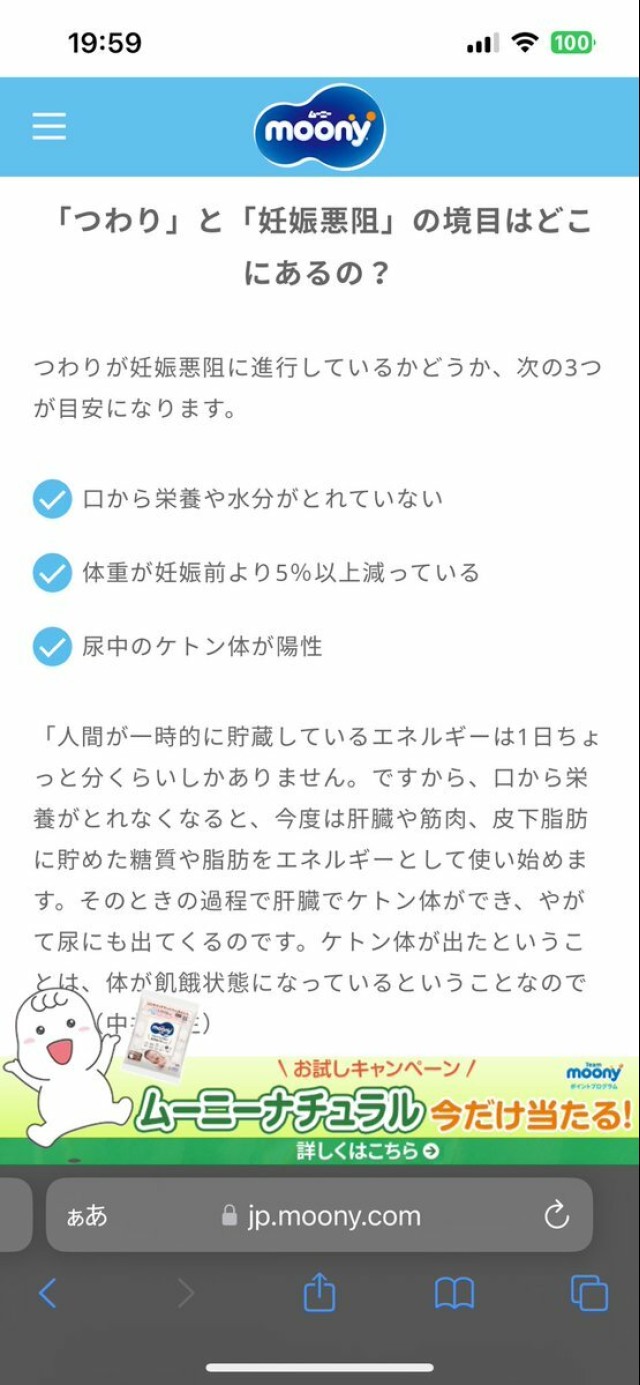

体重管理 ?妊娠前体重より5%以上体重減だと入院治療対象になるようです?水分栄養取れていないようなら、みおさん含めお腹の子の為に、早めに受診された方が良いと思います?